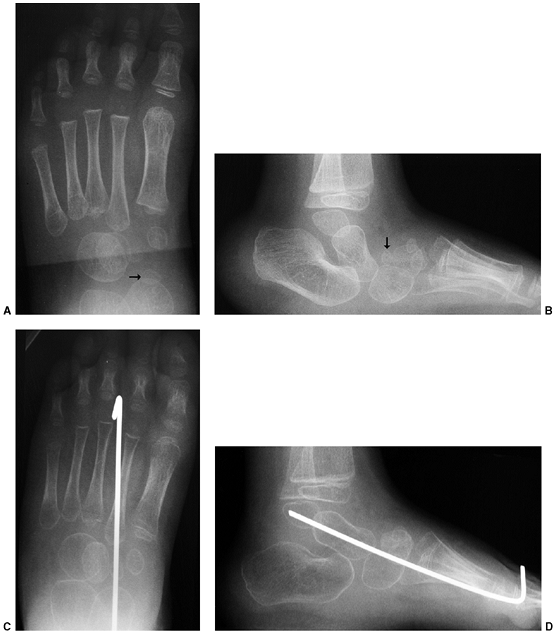

![]() |

|

Figure 30.12 A: This patient had severe cavus deformity as a component of his clubfoot deformity. B:

Following Ponseti management, x-ray films indicate resolution of his cavus deformity with sequential casting and no plantar release. |